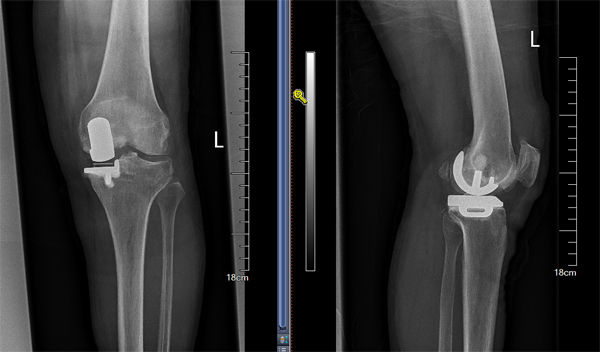

膝关节单髁手术技术从零到有

王伟教授入住骨科后,定期对关节组医师进行授课及专业培训,充分评估患者病情,严格掌握手术适应症,仔细规划术前方案,指导洛阳市中心医院骨科顺利开展膝关节单髁置换手术,实现了该院膝关节单髁置换技术零的突破。目前,该院骨科已能常规开展该技术,促进了洛阳市中心医院关节技术的发展。单髁置换手术是虽然是较为传统的膝关节终末期关节炎的治疗手段之一,早期由于各种原因导致这种优良的手术方式与全膝关节置换术比较发展较为缓慢,但随着近年置换适应症把握、关节假体设计及关节材料的进步多种原因,使单髁置换术成优良的微创保膝治疗手段,在国内外得到广泛的推广。单髁置换术应用于合适的终末期骨关节炎患者后,相比全膝关节置换具有,创伤小,恢复快,病人满意度高等优势,同样得到广大的患者的认可和首选。由于单髁置换讲究更高的置换精度,要求精细,而准确的手术操作,对手术医师的素养具有更高要求,只有具有一定手术量积累的医生,才能获得良好效果,减低手术风险。洛阳中心医院单髁置换手术方式的开展,代表在保膝,微创治疗中迈上一个新台阶。